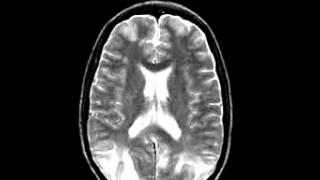

Cerebrovascular Disease Multiple embolic infarction, diffusion and FLAIR imaging

DR. DONG-KYUN KIM

Dr Dong Kyun Kim. Смотреть видео: Degenerative Disease Alzheimers Dementia, Metastatic Carcinoma Of The Colon Spatial, Cerebrovascular Disease Fatal Stroke, Neoplastic Disease Metastatic Adenocarcinoma.